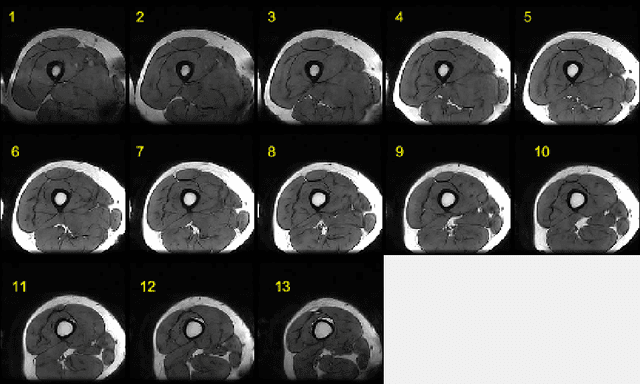

Abstract:This paper presents an end-to-end solution for MRI thigh quadriceps segmentation. This is the first attempt that deep learning methods are used for the MRI thigh segmentation task. We use the state-of-the-art Fully Convolutional Networks with transfer learning approach for the semantic segmentation of regions of interest in MRI thigh scans. To further improve the performance of the segmentation, we propose a post-processing technique using basic image processing methods. With our proposed method, we have established a new benchmark for MRI thigh quadriceps segmentation with mean Jaccard Similarity Index of 0.9502 and processing time of 0.117 second per image.